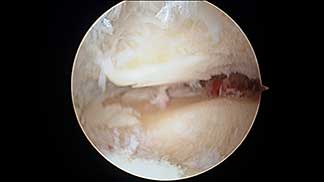

Artroscopia de tobillo

Artrosis de tobillo grado IV, visión artroscópica